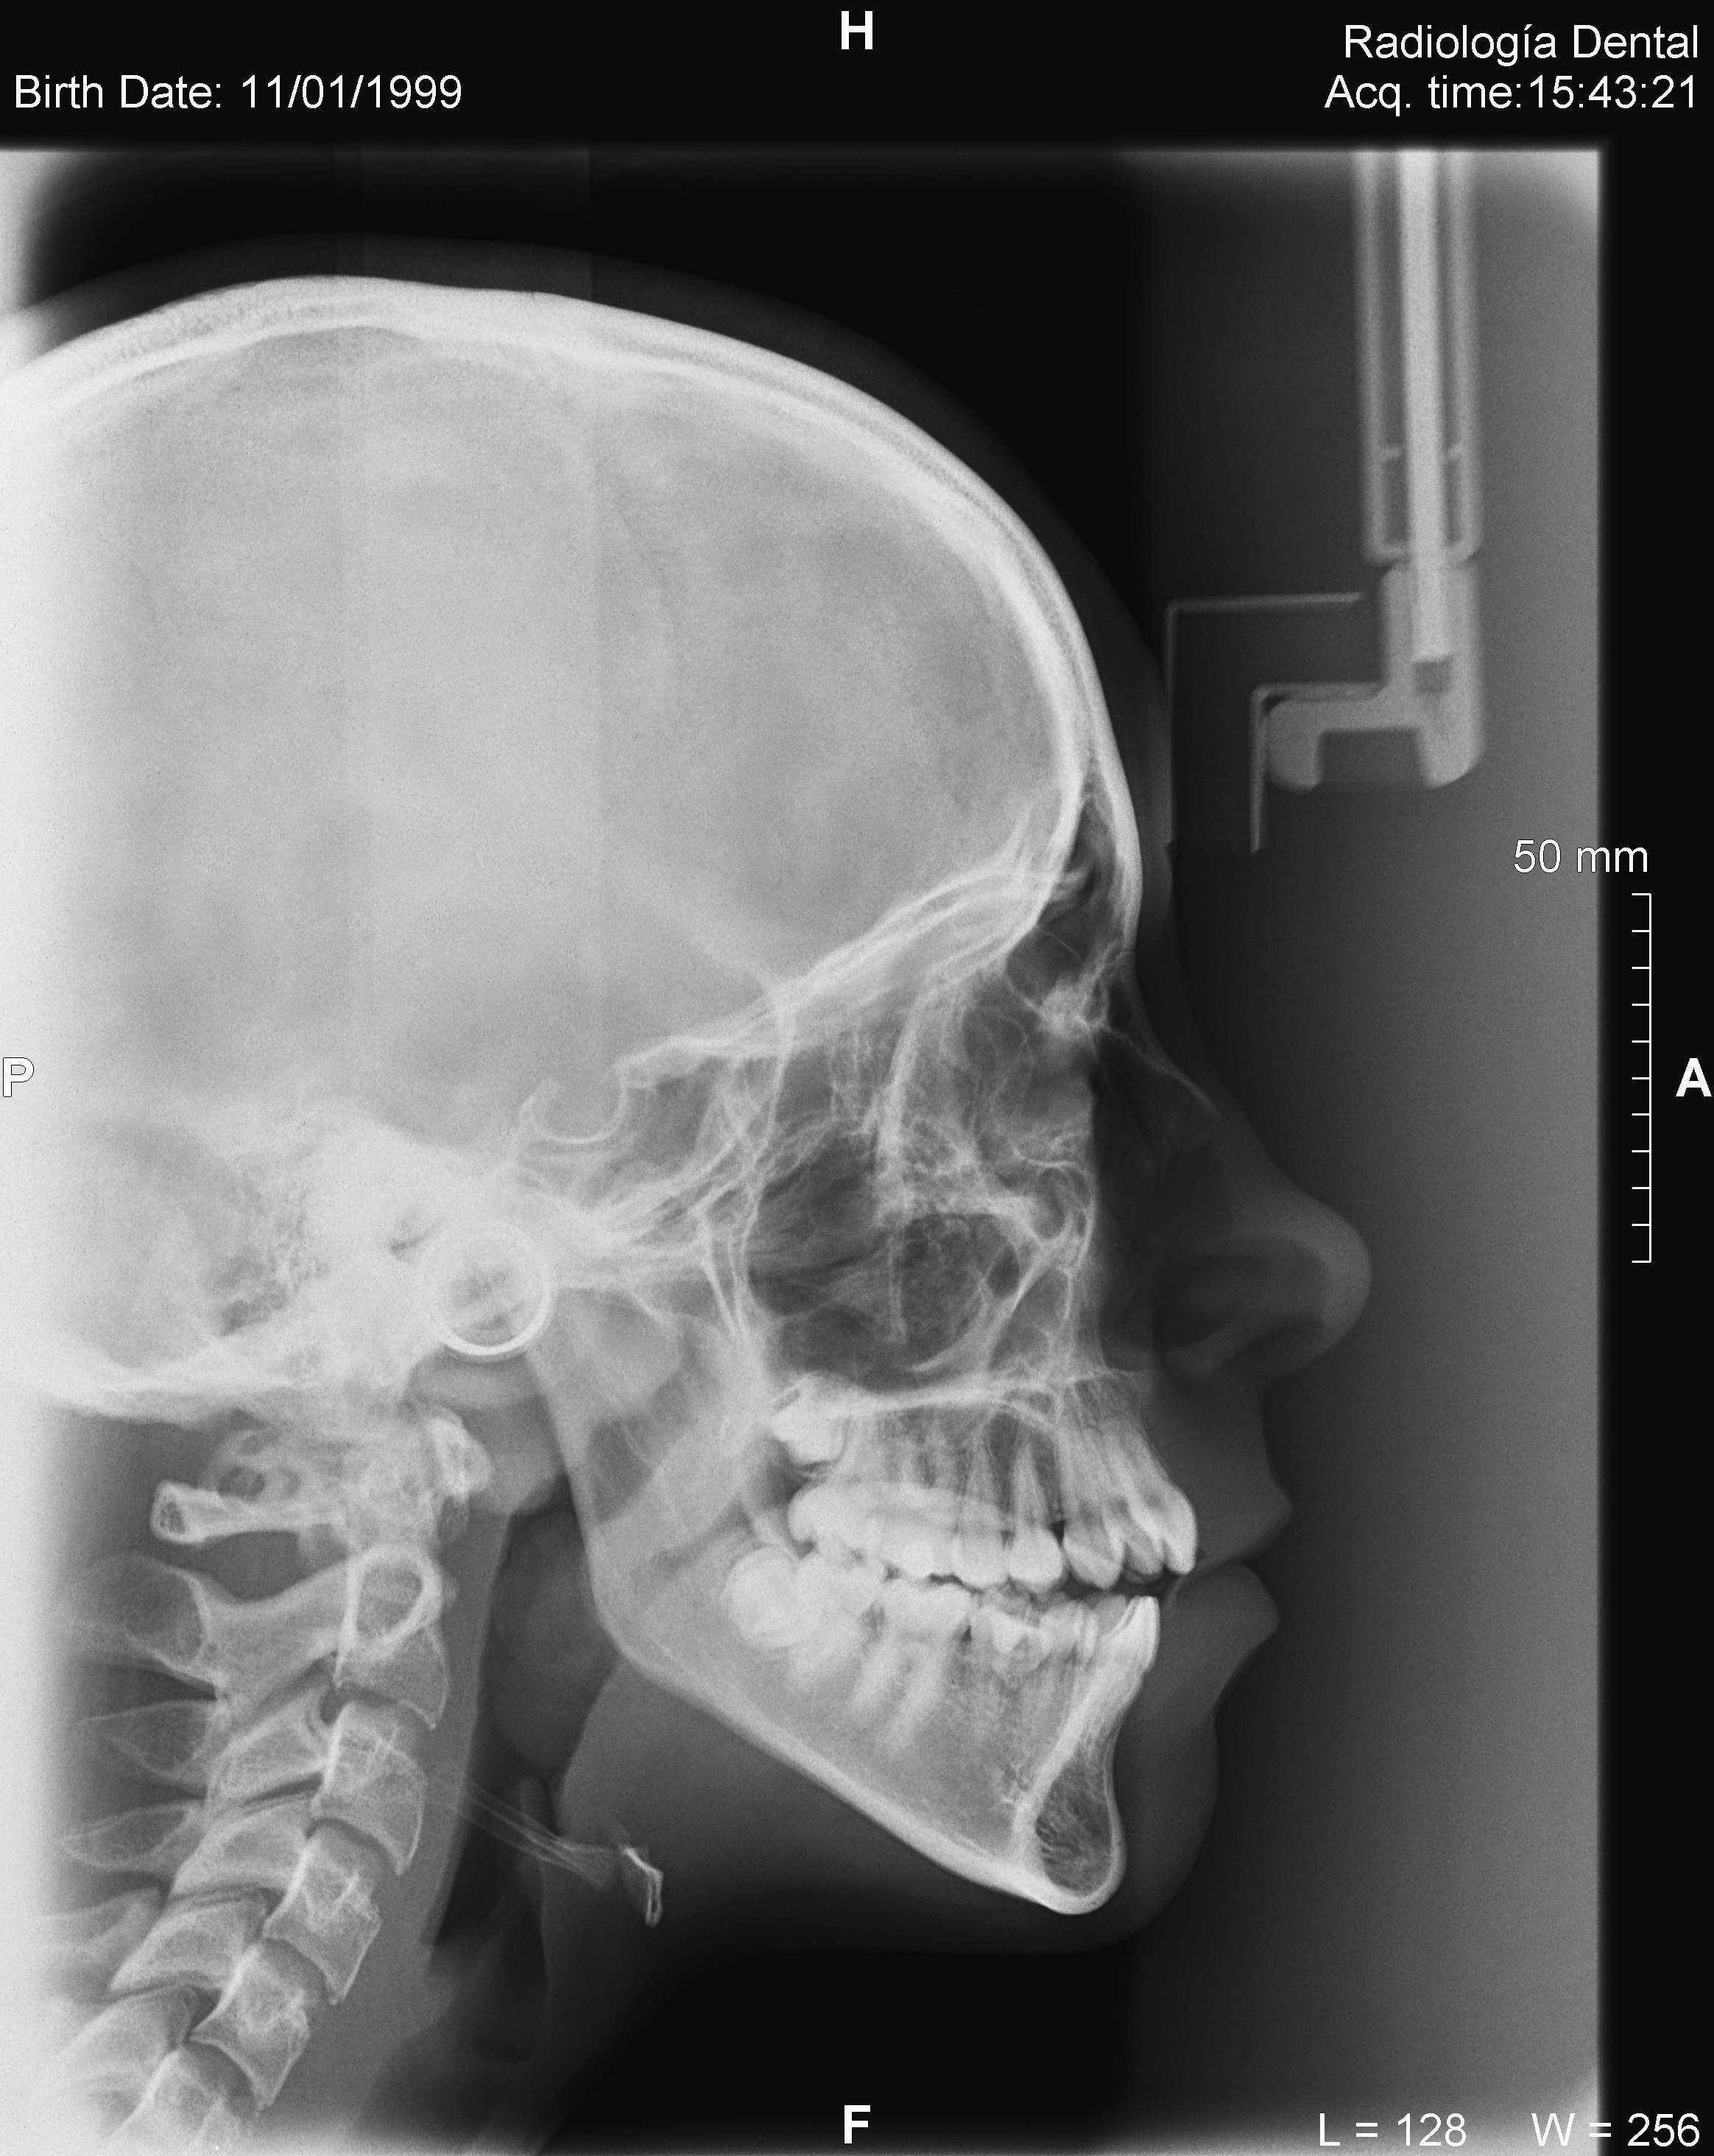

Algunos ejemplos de imágenes digitales

Pulse en las imágenes para ver la ampliación

14lado

• Telerradiografía frontal y lateral digital

• Cefalometría computarizada